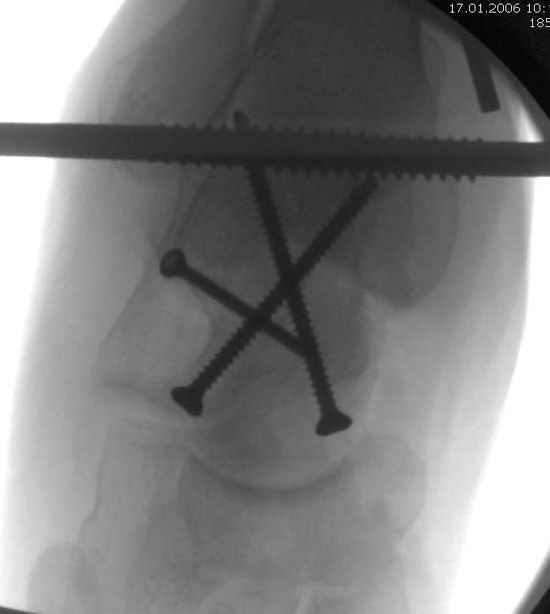

Вдогонку по поводу перелома таранной кости, больная 81, не страдает диабетом, перелом закрытый, в первый же день поступления ограничились временным наружным фиксатором (как на снимке).

Из-за отека на стопе тактика лечения у всех была

одинаковая: временная наружная фиксация до спадения отека, при изолированных переломах они выписывались домой и через дней 7 госпитализировались на оперативное лечение.

Примеры на снимке...